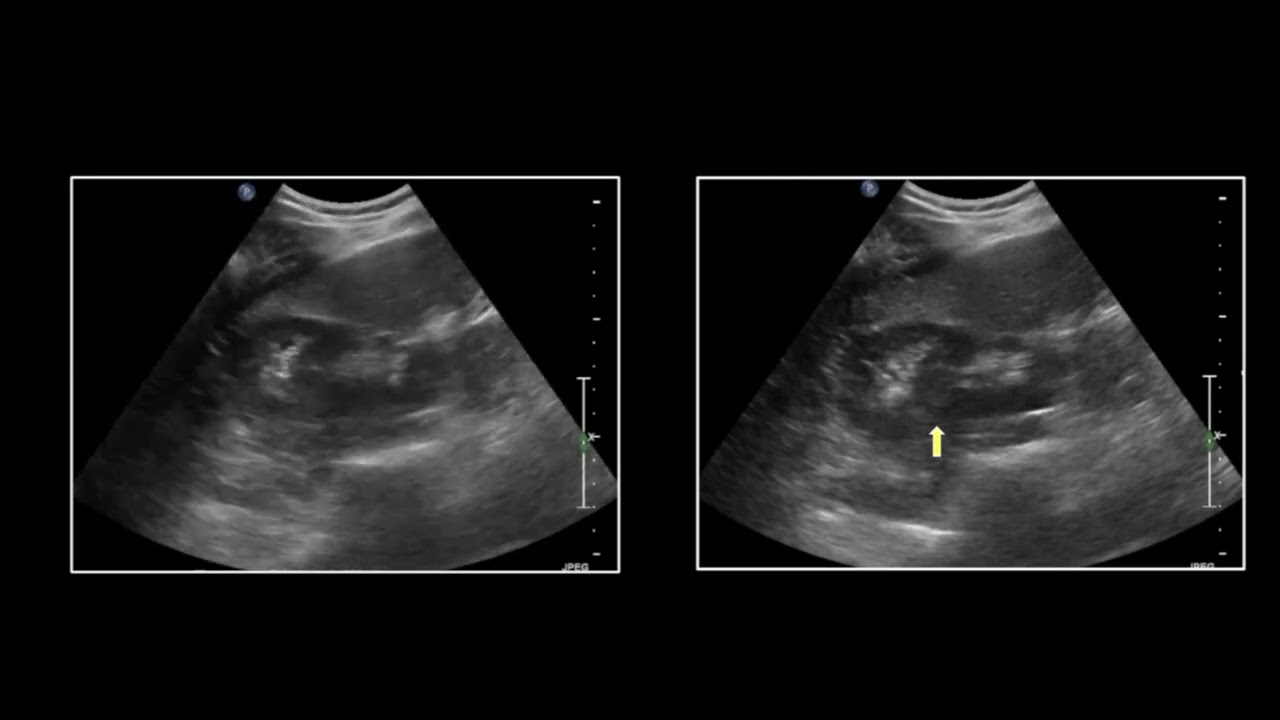

CT of Urinary Pathology 2 | Free Radiology CME

Become familiar with the CT appearance of a variety of abnormalities affecting the kidneys, ureters, and bladder.

Ultrasound of the Abdomen & Pelvis | Free Radiology CME